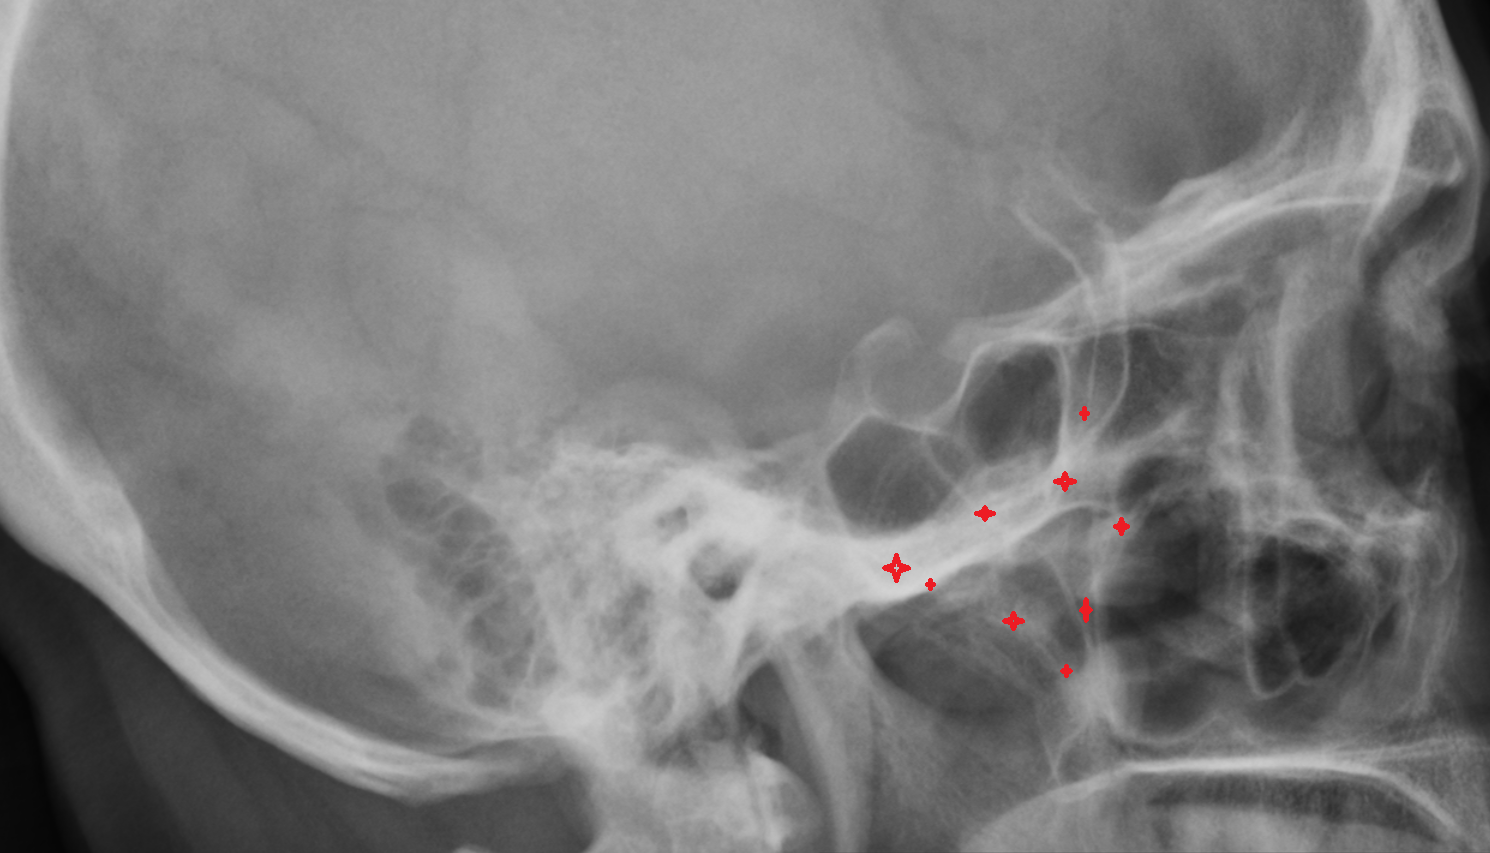

- Cervical spinal nerve 1 (C1)

- Cervical spinal nerve 2 (C2)

- Cervical spinal nerve 3 (C3)

- Cervical spinal nerve 4 (C4)

- Cervical spinal nerve 5 (C5)

- Cervical spinal nerve 6 (C6)

- Cervical spinal nerve 7 (C7)

- Cervical spinal nerve 8 (C8)